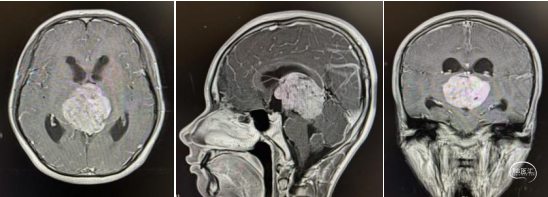

头部MRI显示:松果体区可见一形态不规则肿块,大小约52mm*50mm*51mm,其内信号混杂,呈短-长T1,短-稍长-长T2信号,增强后实质部分可见明显不均匀强化。肿瘤部分突入三脑室内,与三脑室左侧壁及左侧丘脑分界不清,中脑导水管受压变窄,三脑室及侧脑室扩张。右侧脑室前角可见一引流管影。

术前MRI